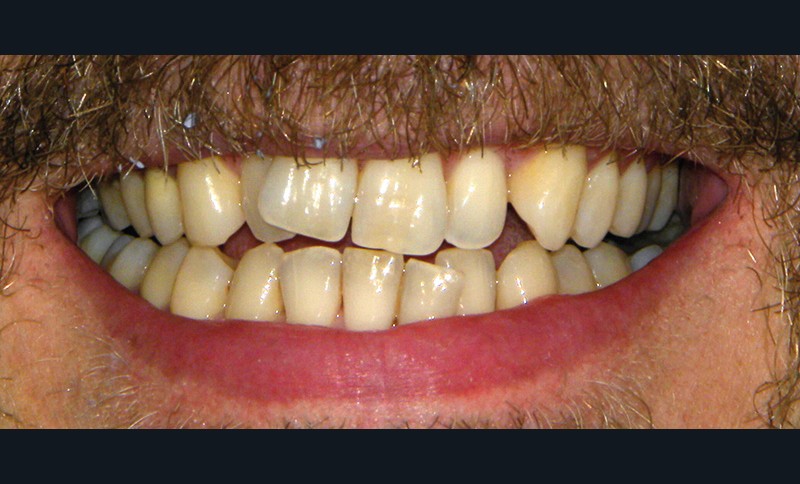

Nicolas D. est un patient de 38 ans qui est venu consulter pour son sourire disgracieux (fig. 1).

Il présente une malocclusion de classe II subdivison gauche totale par mésioposition du secteur 2 avec une déviation dentaire du milieu maxillaire à droite (fig. 2 à 6) dans un visage équilibré (fig. 7 et 8).